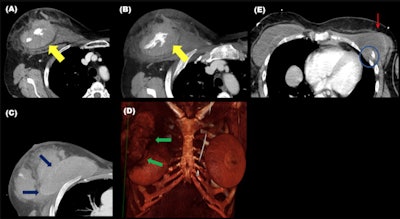

Chest wall injuries tend to align along the axis of the belt. Ribs and sternal fractures are the most common chest wall fractures, but clavicles can also be involved. Sternal fracture is better seen in the sagittal plane and the underlying anterior mediastinal hematoma is better assessed in the axial plane, and fractures of the chondrocostal union are better seen with a soft-tissue window, they stated.

Although rare, breast implant ruptures may occur. These and soft tissue injuries of the chest wall are more frequent when the shoulder harness does not lay over osseous structures.

Fractures of the chest wall are often accompanied by lung contusions and hemopneumothorax. In severe collisions, thoracic aortic rupture through the isthmus or dissection can occur. Other types of intimal injuries are pseudoaneurysms or intimal defects with no aortic contour abnormality.

"Diaphragmatic ruptures are caused by the mispositioning of the lap belt, the sliding of the occupant under the belt during the impact, and the high increase in the intraabdominal pressure," the authors wrote. "They are better assessed in the coronal plane, and fractures or angulation of the ribs and subcutaneous emphysema can be clues."

Abdominal wall hernias occur because of the shearing forces through the myofascial layers of the abdominal wall during the sudden deacceleration and the high increase in the intraabdominal pressure. They occur through the weakest anatomical sites of the abdominal musculature. Multiplanar reformation should be performed to increase sensibility.

"Although they are misdiagnosed clinically, their presence indicates the violence of the accident and they are associated with a high risk of surgical intraabdominal injuries; either herniated intraabdominal structures or structures far from the herniation site," they explained. "Other abdominal wall injuries include soft tissue contusion or direct muscle rupture."